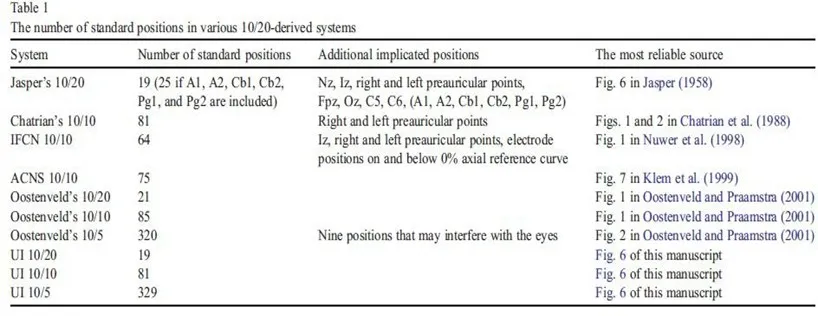

La Sperimentazione Elettroencefalografica

The Ten-Twenty Electrode System of the International Federation

George H. Klem* (USA), Hans Otto Lüders (US), H.H. Jasper (Canada and C. Elger (Geermany)

- The position of electrodes placed should be based on specific measurements of standard skull landmarks. The measurements should be proportional to the size and shape of the skull.

- Adequate coverage of all parts of the head should be provided with standard electrode placement.

- Electrode designations would be expressed in terms of brain areas covered rather than only in numbers. This would make communications more meaningful to the non-spacialist, as well as workers in other laboratories.

Technique of Measurement

The measurement technique is based on standard landmarks of the skull. Namely, the nasion, inion, and the left and right preauricular points. The preauricular points are felt as depressions at the root of the zygoma, just anterior to the tragus.

The first measurement is in the anterior-posterior plane through the vertex, taken from the nasion to the inion. This measurement is divided into 5 separate areas (see fig.1).

The first mark is placed at 10% of the total measurement and labeled Fp. The second, third, fourth and fifth marks are placed at 20% intervals of the total measurement and labeled F, C, P, and O. Note that the O mark would be located at 10% of the measurement above the inion. The expression Fp, F, C, P and O represent the fronto polar, frontal, central, parietal and occipital areas, respectively.

Lateral measurement of the central coronal plane strats at the left preauricular point thrugh the C vertex mark to the right preauricular point (fig.2). A mark is placed at 10% of this measurement over the preauricular points and labeled T.

The expression T represents the temporal area. Marks are then located at 20% of the lateral measurement and labeled left and right C, and the C vertex location is crossed.

A circumferential measurement (fig.3) is then taken over the temporal lobes from the midline Fp position to the midline O position.

A mark is made at 10% of this measurement indicating the left or right Fp electrode position. Marks are then made at 20% of the measurement and are labeled inferior frontal, mid-temporal, and posterior temporal and left or right occipital (note that the mid-temporal electrode positions are crossed). The remaining 10% measurement from the left and right occipital marks would be the midline = position. Variations of this measurement have been described by Harner and Sannit (1974)

Fig.1 Lateral view oof skull to show methods of measurement from nasion to inion at the midline. Fp is frontal pole position, F is the frontal line of electrodes, C is the central line of electrodes, P is the parietal line of electrodes and O is the occipital line. Percentages indicated represent proportions of the measured distance from the nasion to the inion. Note that the central line is 50% of this distance. The frontal pole and occipital electrodes are 10% from the nasion and inion, respectively. Twice this distance, or 20% separates the other lines of electrodes

Fig.2 Frontal view of the skull showing the method of measurement for the central line of electrodes as described in the text.

Fig.3 Superior view with cross section of skull through the temporal line of electrodes illustrating the 10-20 system applied in this direction as described in the text

Antero-posterior measurements are taken from the left and right Fp position through the lateral C position to the left and right O position. This measurement is then divided equally by 25% marks and labeled lateral F, lateral C, and lateral P. Anterior coronal measurements are taken from the left and right inferior frontal position through the midline F position and divided into 25% segments, making crosses at the left lateral frontal, F vertex and right lateral frontal positions. A posterior coronal measurement is taken from the left posterior temporal mark through the midline P position and this is also divided into 25% segments and marks are labeled left lateral P, midline P and right lateral P (fig.4)

These measurements provided for the location of 19 of the 21 electrodes used in the 10-20 electrode system (fig.5). The remaining two electrodes were placed on the ear loves and labeled auricular electrodes. The electrode positions were named in anatomical terms for the cortical areas rocerded, with the exception of the “C” electrodes which were termed central since they were located over the central sulcus.

A numbering system was added to differentiate between left and right homologous regions, odd numbers for the left hemisphere, Fp1, F3, F7, C3, T3, P3, T5, and O1. Even numbers for the right hemisphere, Fp2, F4, F8, C4, T4, P4, T6, and O2. The original recommendation called the F, C and P vertex electrodes F0, C0, and P0, but later changed to Fz, Cz, and Pz (z for the zero).

The numbers selected allowed for the additional electrodes to be placed in the coronal plane and have suitable designations (e.g. F2 placed between Fz and F4, and F6 placed between F4 and F8). Other additional electrodes included pharyngeal and cerebellar elelectrodes which were termed Pg, Pg2, Cb1, and Cb2, resspectively.

Anatomical Studies

Anatomical studies were performed on the heads of cadavers to determine the cortical areas covered by each electrode position. Measurements were taken and the 10-20 system marked on the skulls, and electrodes were applied. Drill holes were placed through the skull and the underlying cortex was marked with India ink before removing the brain for examination. It was concluded that while there was some variability, the two principle fissures, central and sylvian, were within ±1cm of the marks shown on Fig.6.

Fig.4 the lateral view of left and right hemipshere showing all standard electrode psositions, omitting intermediate positions (such as C5 and C6) which are used only for special studies with more closely spaced electrodes. These drawings were made from a series of X-Ray projections with true lateral views. The location of principal fissurees was determined by silver clips placed at operation and bu other anatomical studies described in the text. The location pf pharyngeal electrodes (pg and Pg2) wal also obtained from X-Ray studies with these electrodes in place.

Fig. 6 A single plane projection of the head, showing all standard positions and the location of the rolandic and sylvian fissures. The outer circle was drawn at the level of the nasion and inion. The inner circle represents the temporal line of electrodes. This diagram provides a useful stamp for the indication of electrode placements in routine recording.

Fig. 7 Modified combinatorial nomenclature